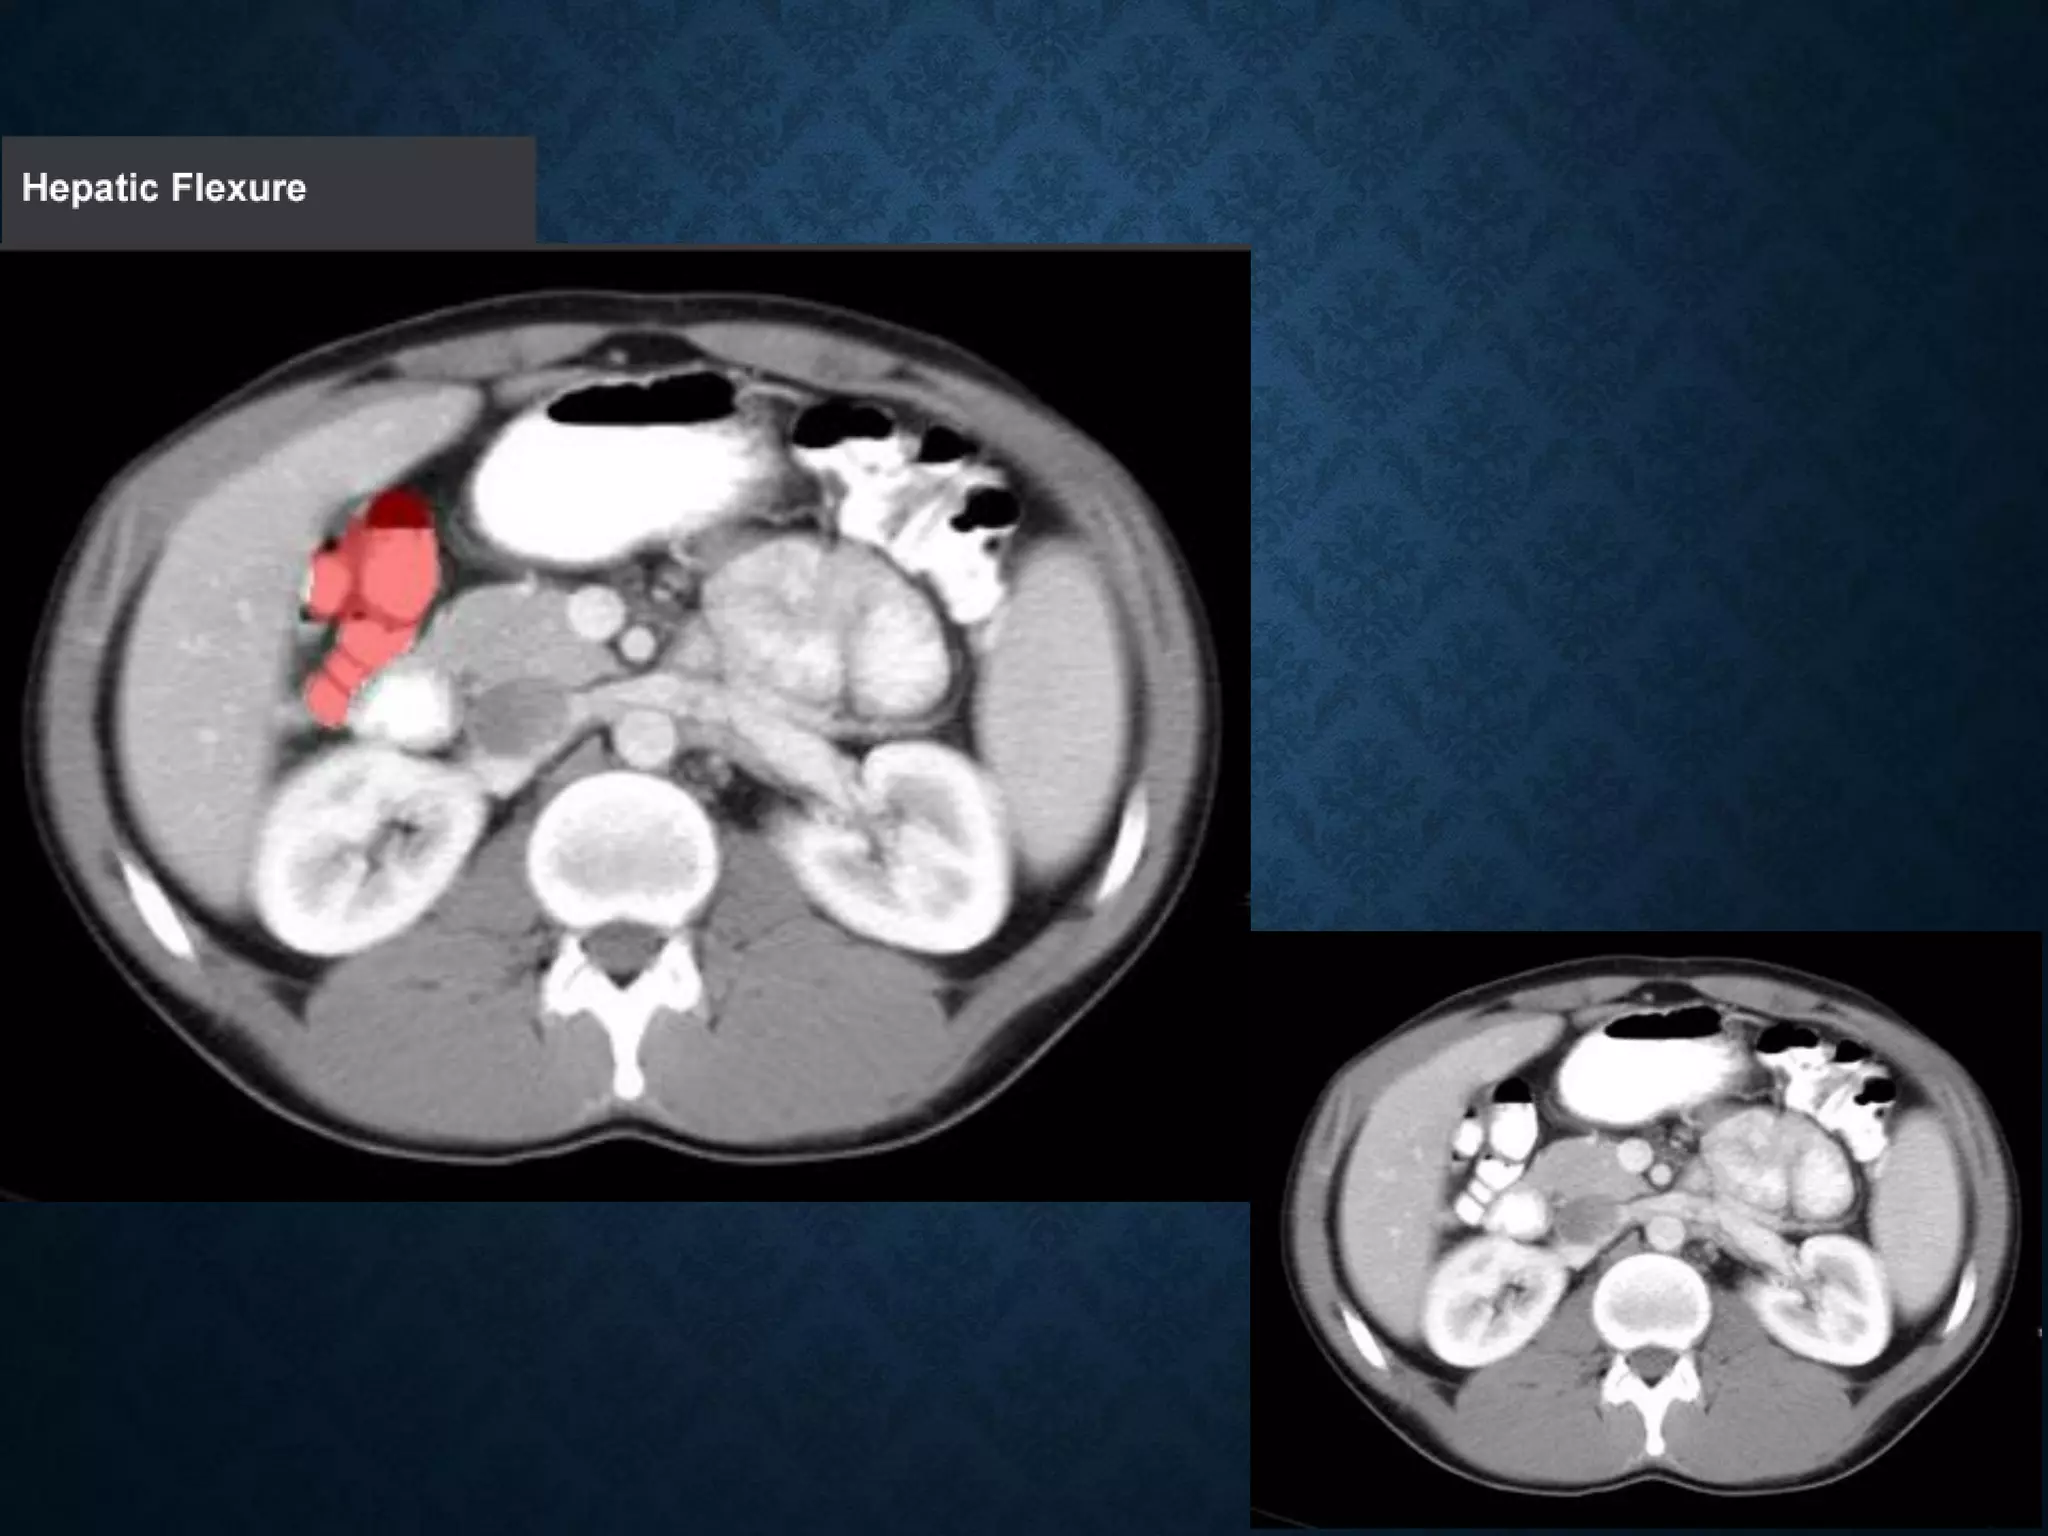

Identify the following structures in the body CT to the right. To view the location of the structure in the image click on

the label at the left and the structure will be indicated in the image. Abdominal CT scans typically begin just above

the diaphragm, so the first slice you see is of the lower chest.